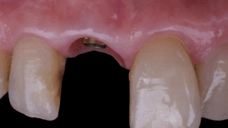

The surgical protocol began with the atraumatic extraction of tooth 1.1 to preserve as much of the alveolar socket as possible. Immediately following extraction, an N1 implant was placed into the socket using a guided surgical approach to ensure ideal three-dimensional positioning. The “one abutment one time” technique was applied to minimize soft tissue manipulation during the healing phase, which is particularly important in esthetic areas.

Given the significant buccal defect, guided bone regeneration (GBR) was performed simultaneously. A mixture of autologous bone and creos™ xenogain™ was applied to the defect and covered with a resorbable creos™ membrane to restore ridge width and support the buccal contour. In addition, a connective tissue graft was harvested and placed in the vestibular region to increase the thickness of keratinized mucosa. This combined approach addressed both hard and soft tissue deficiencies, providing the biological foundation for a stable and esthetic outcome.

On the same day as the surgery, an immediate-load provisional crown was delivered. This restoration was fabricated in acrylic resin and screw-retained on the implant, following the “one abutment one time” principle. The provisional crown was carefully adjusted to avoid occlusal loading while supporting the peri-implant soft tissue architecture during the healing phase.